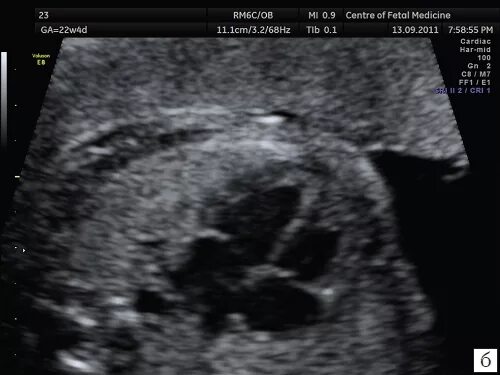

Сердце визуализация затруднена